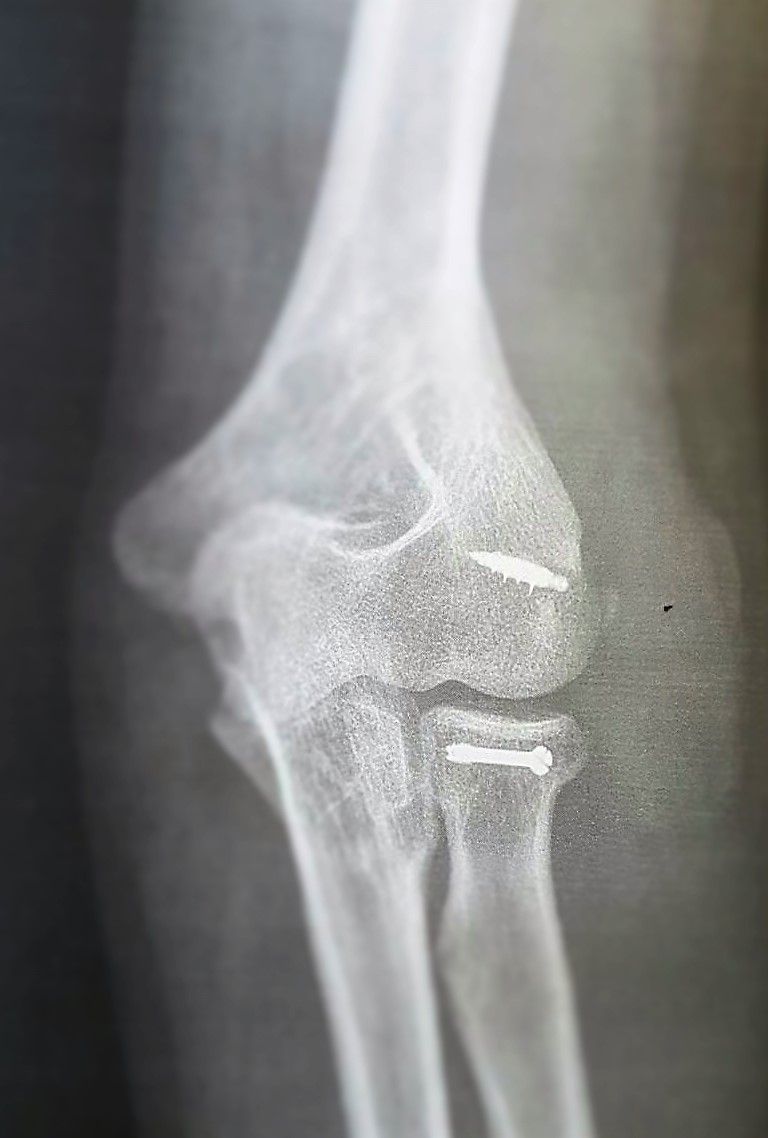

Specialista di chirurgia della Spalla, del Gomito e di traumatologia dello sport. Opinion leader e docente di fama Europea della patologia dell'arto superiore, con particolare interesse verso le ricostruzioni legamentose, l'artroscopia, la sostituzione protesica ed interventi di revisione. Gran parte della mia pratica clinica e chirurgica è attualmente il trattamento di fallimenti di altri interventi o traumi non guariti correttamente e il trattamento dell'atleta ad alto livello con patologie di spalla e gomito.

Parallelamente all'attività chirurgica di revisione ho da sempre approfondito la chirurgia mini invasiva dell'arto superiore, soprattutto sviluppando techniche chirurgiche come l'artroscopia di gomito e la fissazione esterna per le fratture di omero prossimale.

Most of my surgical practice is currently the treatment of failures of prior surgeries and post traumatic deformities. I'm also greatly involved in the treatment of high level athletes and I developed my skills in mini-invasive surgeries, especially elbow arthroscopy and mini-invasive techniques for the treatment of proximal humeral fractures.